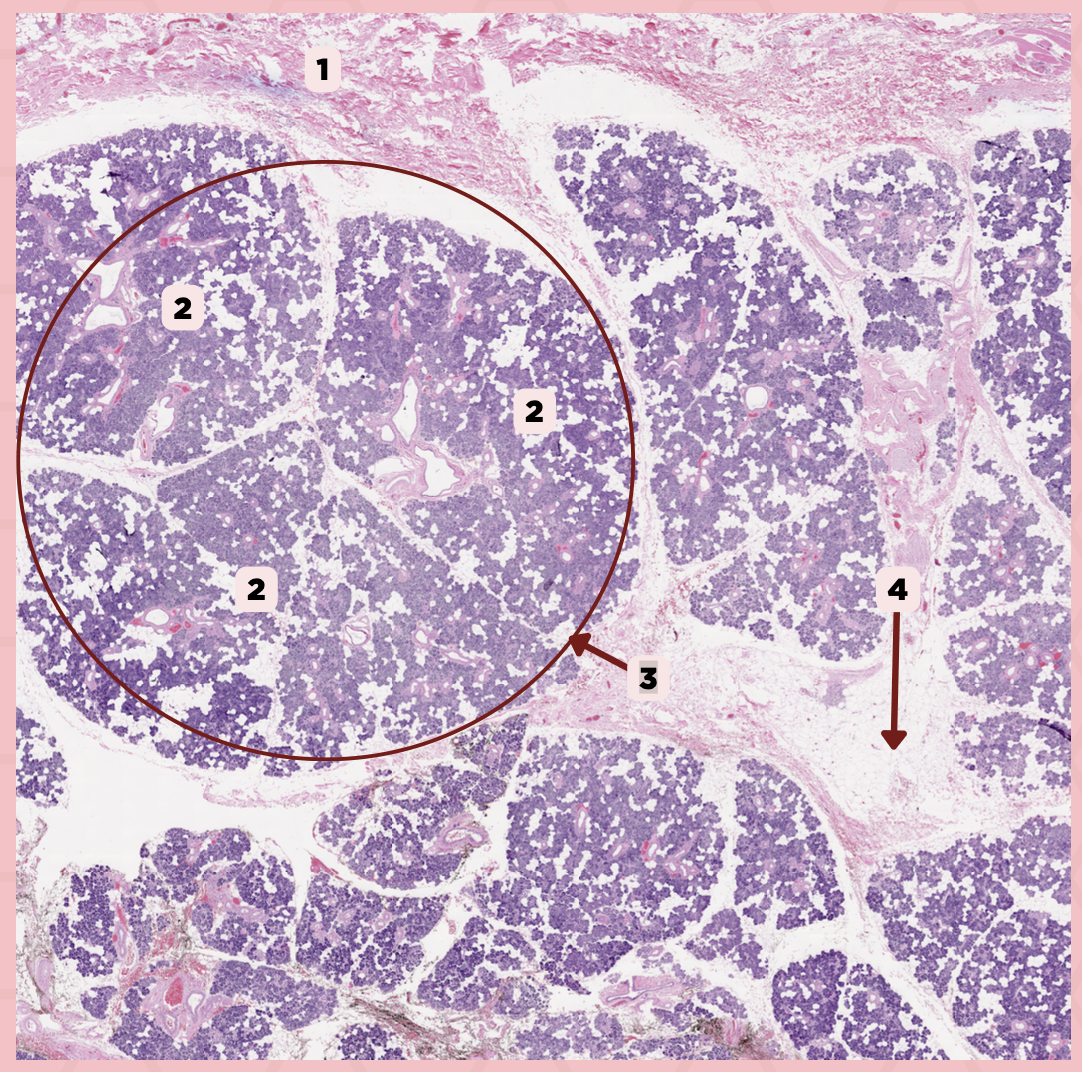

Parotid

Identify the specimen.

Capsule

Identify the structure labeled as 1.

Lobule

Identify the structure labeled as 2.

Lobe

Identify the structure labeled as 3.

Connective Tissue

Identify the structure labeled as 4.

Parotid

Identify the specimen.

Adipocyte

Identify the structure labeled as 1.

Connective Tissue

Identify the structure labeled as 2.

Intercalated Duct

Identify the structure labeled as 3.

Striated Duct

Identify the structure labeled as 4.

Serous Gland

Identify the structure labeled as 5.

Submandibular

Identify the specimen.

Capsule

Identify the structure labeled as 1.

Septa

Identify the structure labeled as 2.